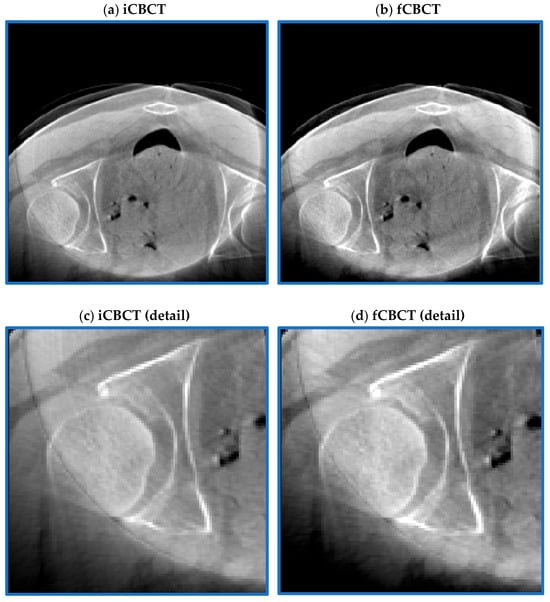

3.4. Qualitative Evaluation